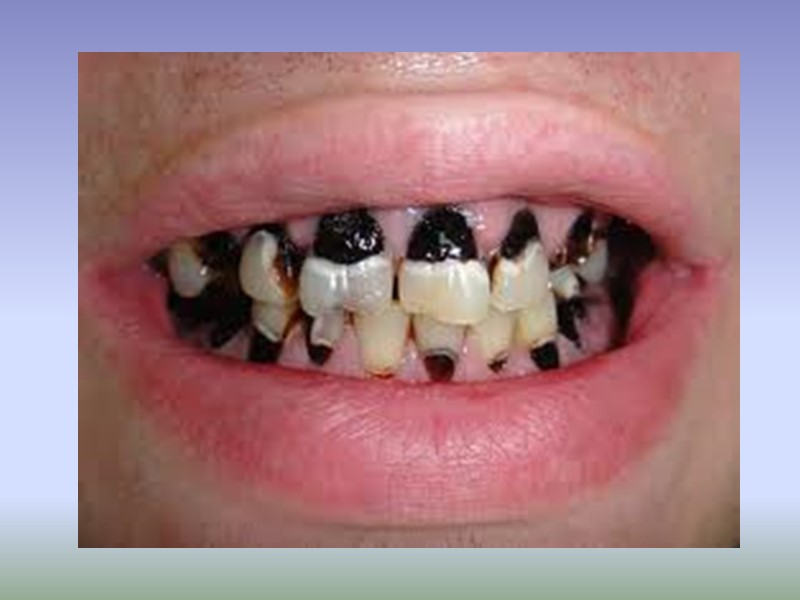

Классификация кариеса МКБ-10 К02.0 Кариес эмали К02.1 Кариес дентина К02.2 Кариес цемента К02.3 Приостановившейся кариес зубов К.02.3 Одонтоклазия Детская меланодентия Меланодонтоклазия К02.8 Другой кариес зубов К02.9 Кариес зубов неуточнённый

Классификация по локализации: Фиссурный кариес. Контактный (апроксимальный) кариес. Пришеечный (цервикальный) кариес. Циркулярный (кольцевой) кариес.